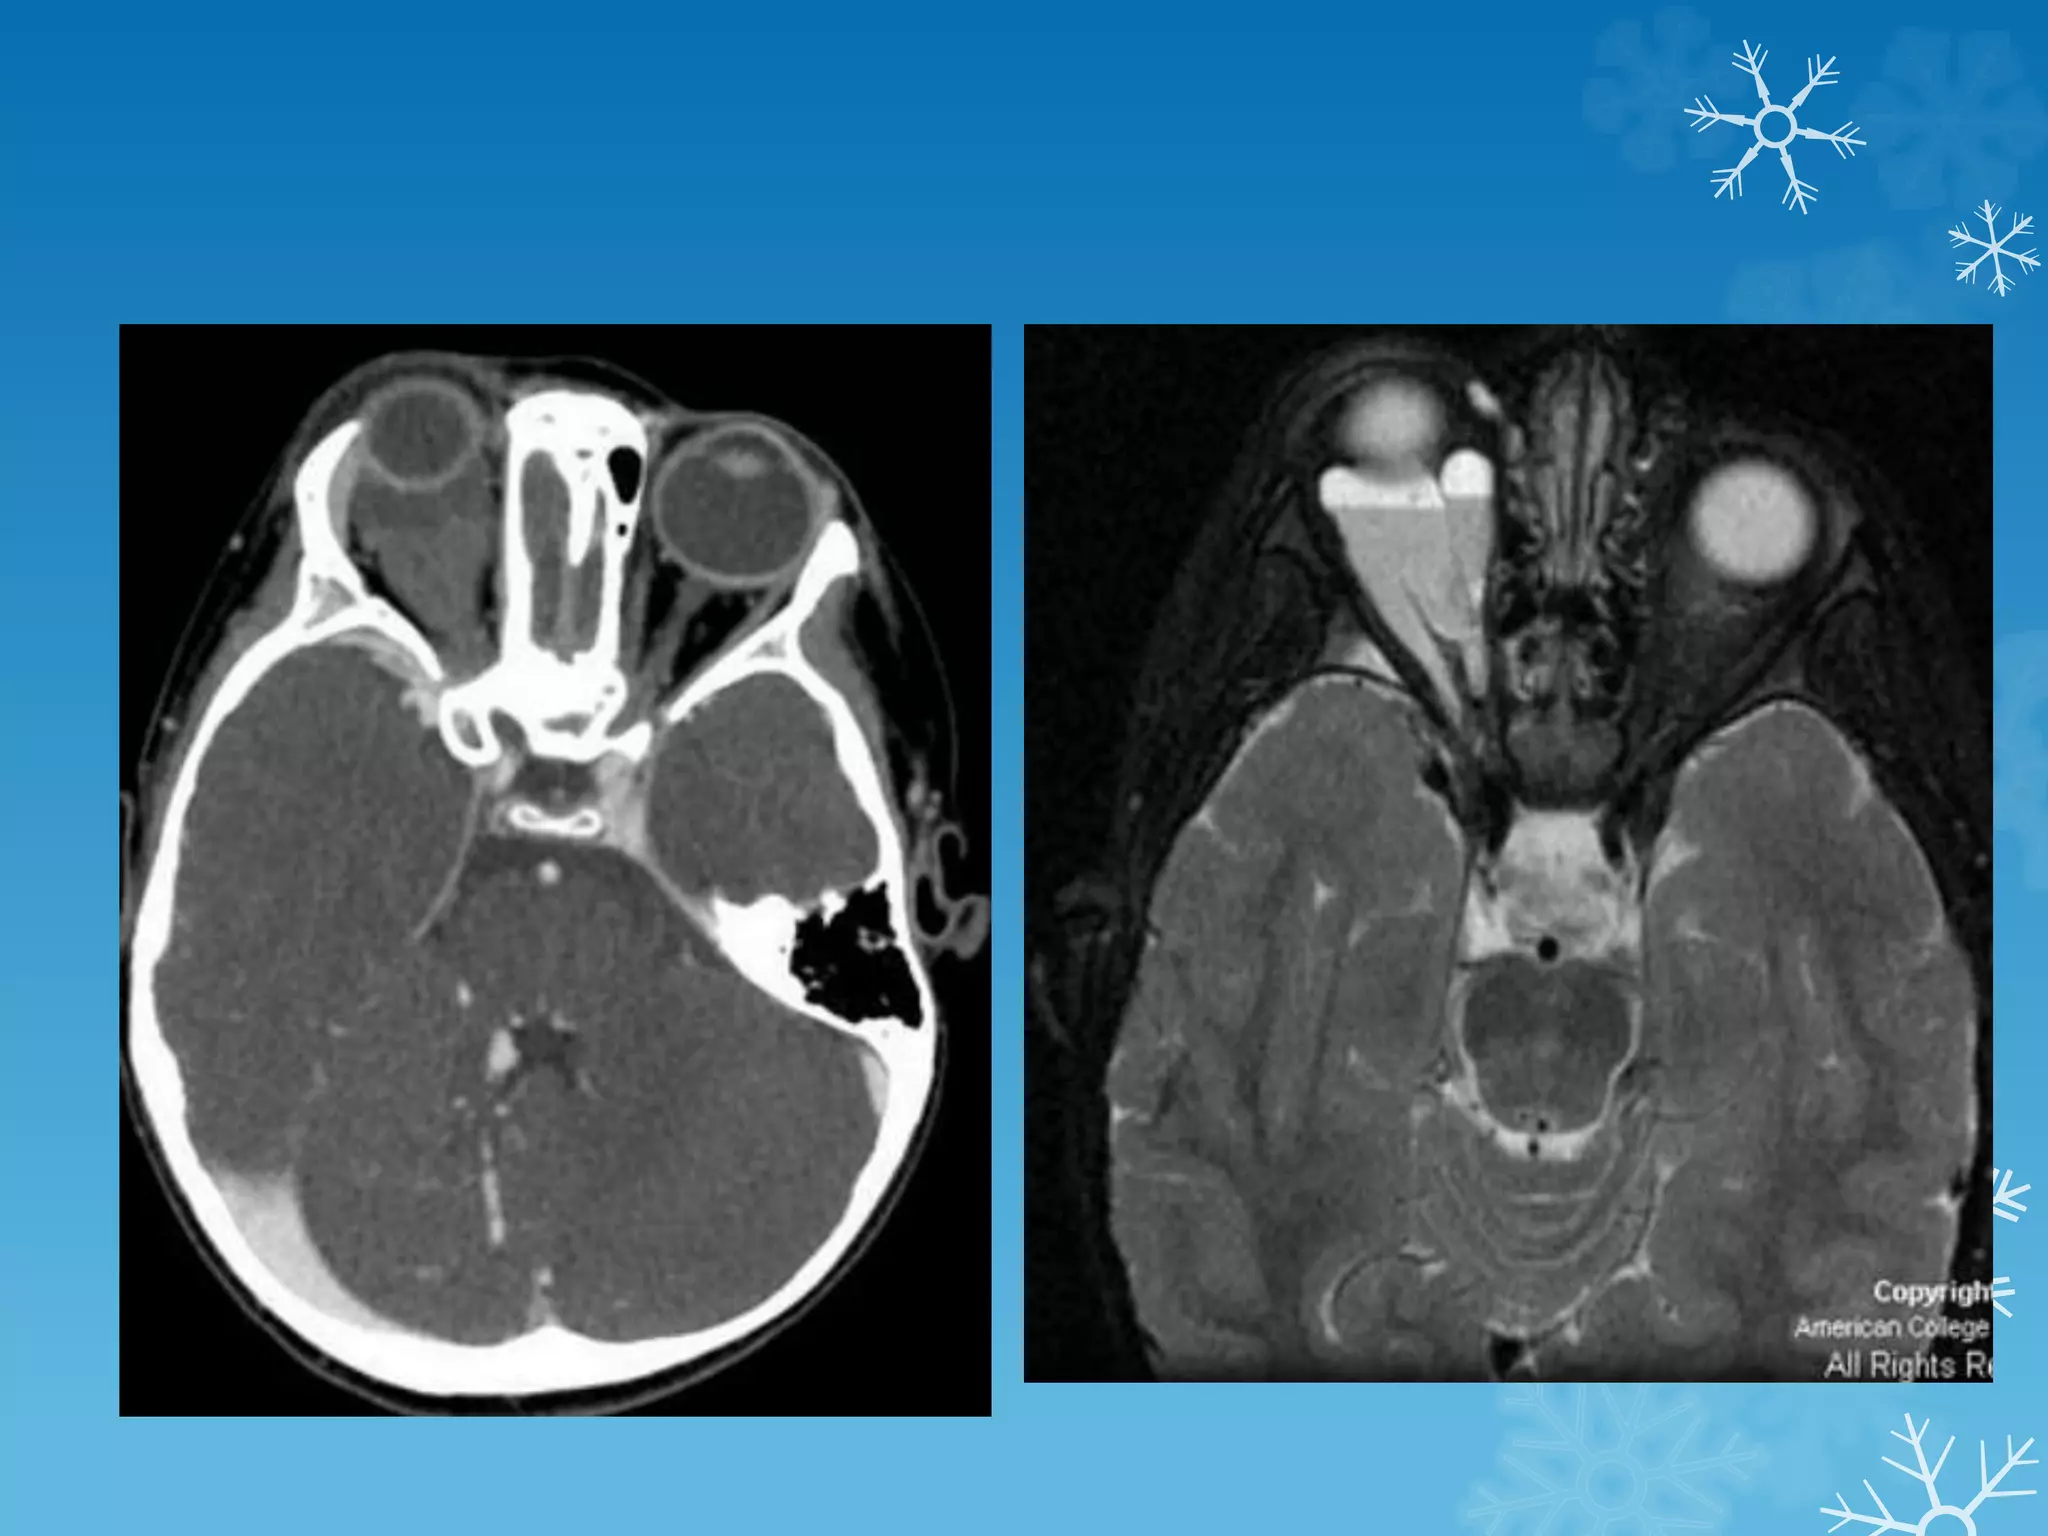

SPOT 5

CT MRI

Endolymphatic sac tumors (ELSTs)